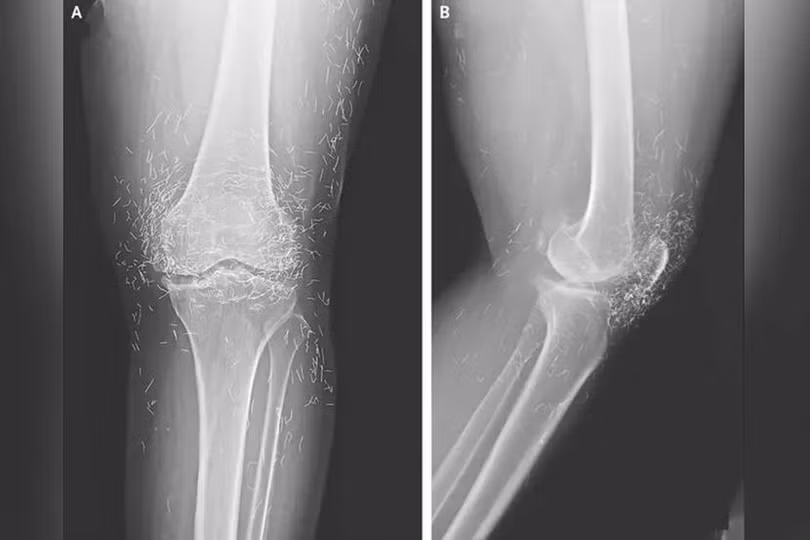

Ảnh chụp X-quang cho thấy hàng trăm sợi chỉ vàng trong đầu gối của nữ bệnh nhân. Ảnh: OddCentral.

Kết quả chụp X-quang cho thấy tình trạng dày và cứng bất thường ở phần xương chày trong, sự phát triển của gai xương quanh đầu gối – những triệu chứng điển hình của thoái hóa khớp – cùng với hàng trăm sợi chỉ vàng li ti được cấy vào các mô quanh khớp.